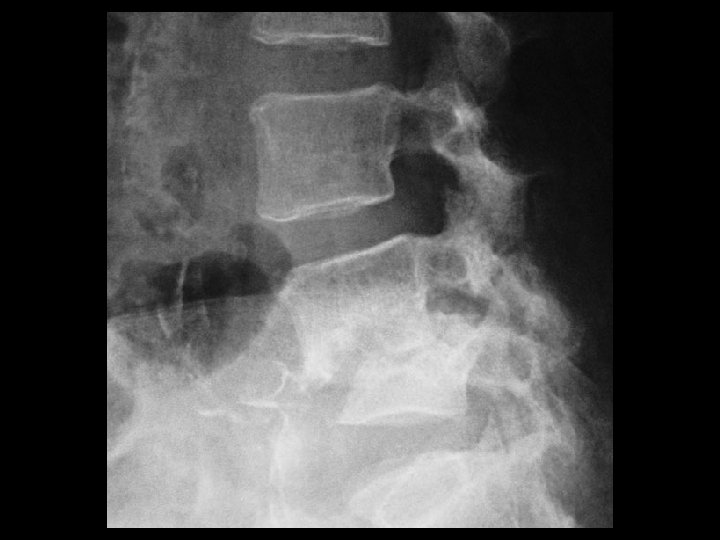

Discitis/Osteomyelitis • Findings: – L 4 -5 disc space and adjacent endplate sclerosis and destruction – ~50% anterolisthesis and gibbus deformity • ddx: – NONE! – This is an Aunt Minnie!